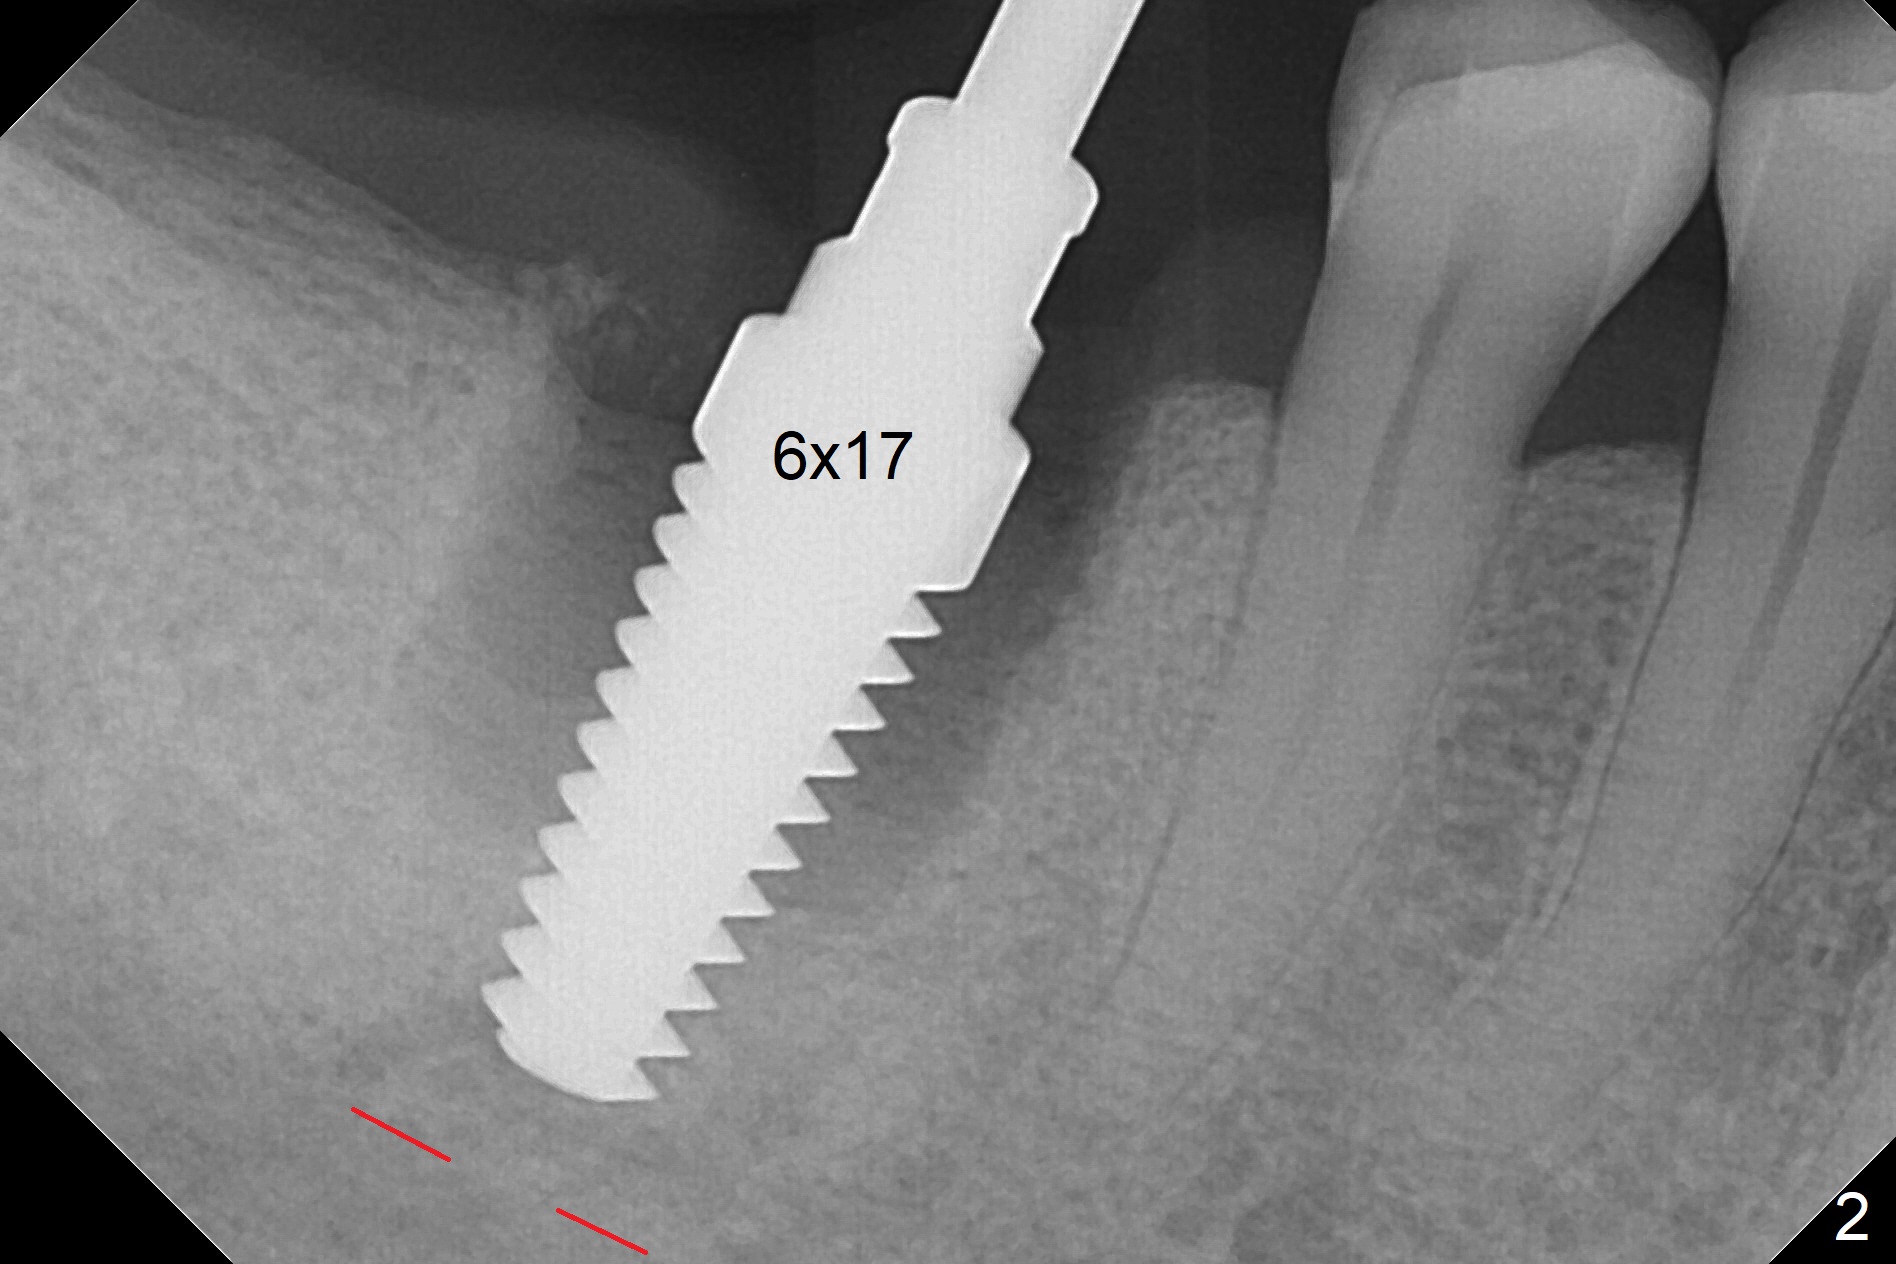

After extraction of the tooth #30 and curettage, the septum becomes so thin that the most coronal portion has to be removed with Rongeur and surgical fissure bur (bone height reduction). Initial osteotomy depth is ~ 4 mm from the flattened septum (Fig.1 (yellow dashed line: apical end of the osteotomy)). Following sequential osteotomy (with intact osteotomy wall), a 6x17 mm tap is placed with apparent clearance from the Inferior Alveolar Canal (Fig.2). When the same size implant is placed with 60 Ncm (Fig.3), the nervous patient feels that the implant is too long (causing pain). CT (Fig.4) and panoramic X-ray (Fig.5) show limited clearance (1.4 mm), but compression of the canal due to high torque could not be ruled out. Since limited amount of the native bone (4.1 mm) for primary stability, the implant is not backed up immediately. Vanilla graft is placed after fabrication of an immediate provisional (Fig.6 *). In brief, immediate implant should be avoided when the septum is thin or the native bone is less than 5 mm (3 mm for primary stability; 2 mm for clearance). In fact the implant has to be untorqued 4-5 times of turn to relieve pain nearly 1 month postop. The patient returns for impression 5 months postop (4 months post implant back up, Fig.7). When the abutment is changed to 5x5 mm and prepared, she reports earache (residual nerve damage?). The patient has had the similar complaint 9 months postop; it appears that there is radiolucency distally (Fig.8 >, as compared to radiopaque mesially (*)). The distal gingiva is tender. With a remade permanent crown, oral hygiene instruction is provided. If necessary, CBCT is taken with possible bone graft.